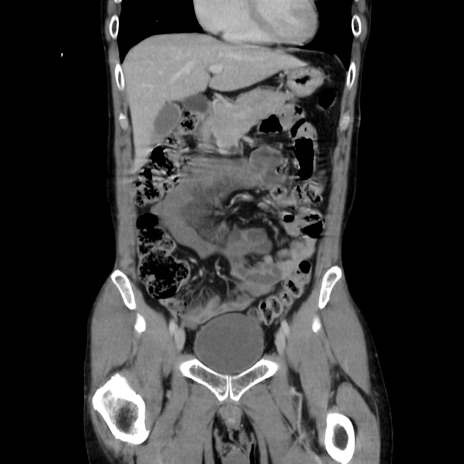

症例37(冠状断像)

【症例】40歳代 男性

【主訴】腹痛

【現病歴】4時間ほど前に電車に乗車中に臍部上より腹痛出現。徐々に増悪し起立困難となり、救急外来受診。生ものは数日食べていない。今朝お雑煮を食べた。

【身体所見】BT 36.8℃、BP 117/84mmHg、HR 91/min、SpO2 97%、苦悶様、腹部:臍上部広範囲圧痛あり、反跳痛±

【データ】WBC 8100、CRP 0.03